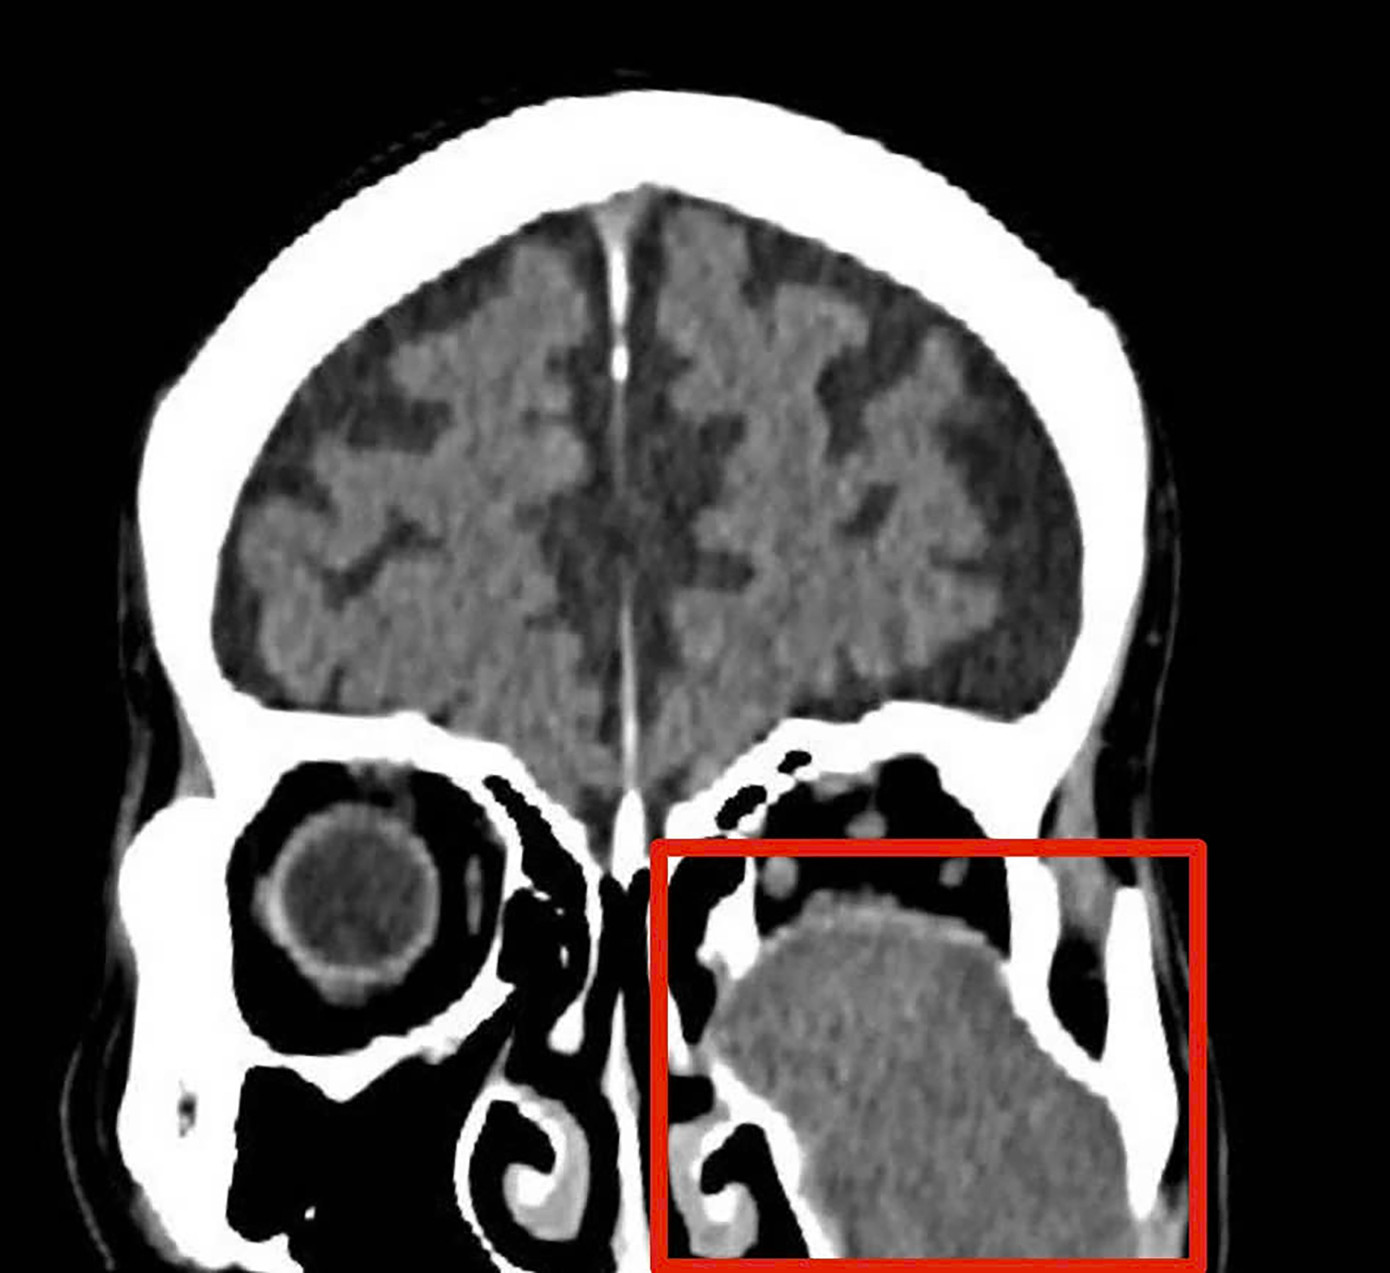

Hình ảnh chụp phim cho thấy khối u ăn mòn tiêu xương sàn ổ mắt.

Kết quả chụp chiếu và hội chẩn liên khoa xác định, khối u nhầy xoang hàm trái của bệnh nhân có kích thước lớn, đã ăn mòn tiêu xương các thành xoang hàm, đồng thời xâm lấn và làm tiêu xương sàn ổ mắt.